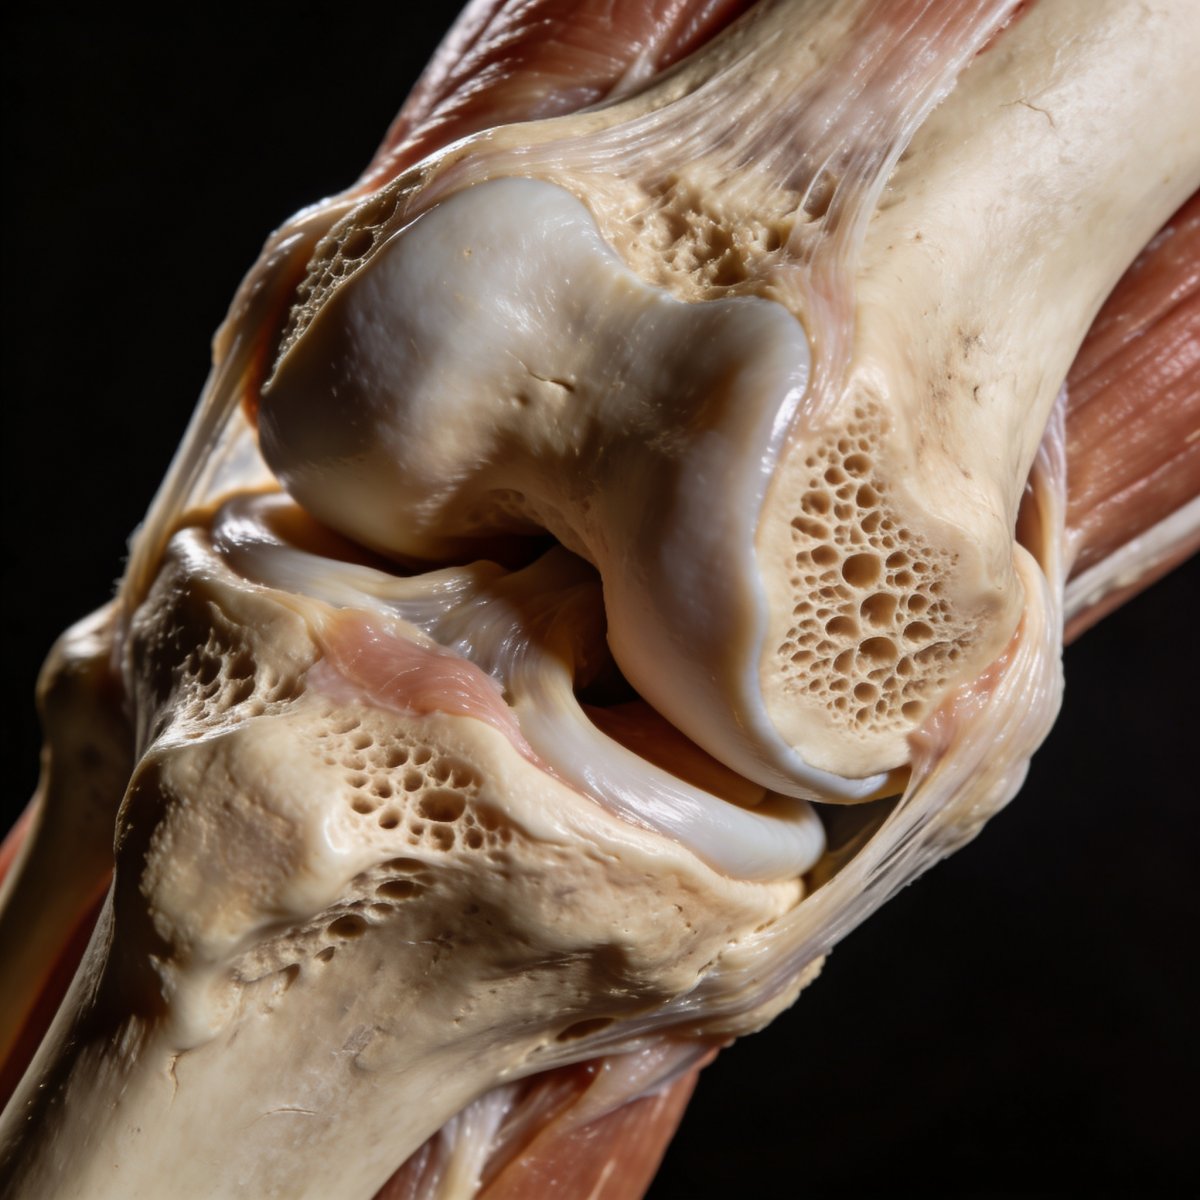

Зона роста, известная также как эпифизарная пластинка или хрящевая пластинка роста, представляет собой хрящевую область, расположенную на концах длинных костей у детей и подростков. Именно в этой зоне происходит активное деление клеток, что обеспечивает увеличение длины костей и, соответственно, рост ребенка. Важность зоны роста невозможно переоценить, поскольку она является «фабрикой» по производству новой костной ткани.

По сравнению с остальной частью кости, хрящ зоны роста менее прочен, что делает ее наиболее уязвимой к травмам. В момент удара или падения, когда взрослый человек получил бы перелом самой кости, у ребенка под воздействием той же силы может произойти перелом именно в области эпифизарной пластинки. Это объясняет, почему детский скелет имеет свои уникальные особенности повреждений. Понимание этой анатомической и физиологической особенности является ключом к адекватной оценке травмы и выбору правильной тактики лечения.